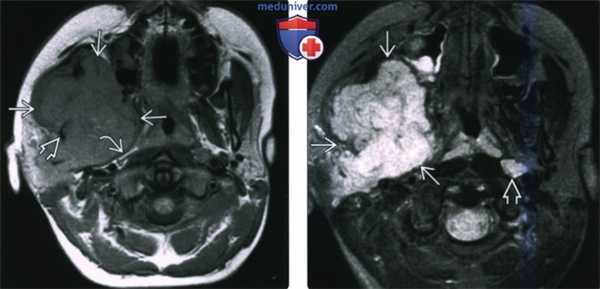

(Слева) При МРТ Т1ВИ в аксиальной проекции определяется объемное образование с сигналом промежуточной интенсивности, которое деформирует жевательное пространство и смещает кпереди заднюю стенку левой верхнечелюстной пазухи. Во всех последовательностях видны небольшие участки низкой интенсивности сигнала, которые представляют собой кальцификаты.

(Справа) МРТ Т2ВИ в аксиальной проекции, этот же пациент. Новообразование имеет гиперинтенсивный сигнал, характерный для опухолей хрящевой ткани. (Слева) МРТ Т1ВИ с КУ, аксиальная проекция, этот же пациент. Образование имеет неоднородную структуру и интенсивно накапливает гадолиний.

(Справа) КТ с КУ в аксиальной проекции, костное окно, этот же пациент. Определяется крупное новообразование, в толще которого «рассеяны» кальцификаты, образующие кольца и арки. Это типичные хрящевые кальцификаты. Наличие кальцификатов обычно говорит о низкой степени злокачественности опухоли.

(Слева) КТ в костном окне, аксиальная проекция. Типичная хондросаркома височно-нижнечелюстного сустава низкой степени злокачественности. Определяются небольшие кальцификаты дистрофической природы (либо кальцифицированный матрикс самого образования) и обширная деарукция/ремоделирова -ние суставной ямки.

(Справа) MPT Т2ВИ в аксиальной проекции, тот же пациент. Определяется дольчатое гиперинтенсивное образование с четкими контурами, которое окружает мыщелок нижней челюсти.